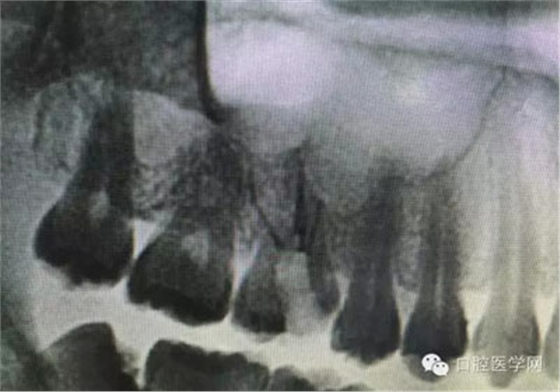

根管治療,我們?cè)诖髮W(xué)的時(shí)候就學(xué)習(xí)的東西,標(biāo)準(zhǔn)就在那里放著,可是很多時(shí)候我們熟視無睹,放任我們的想象去做。我們多些重視,多些心思,會(huì)好很多,認(rèn)真對(duì)待每顆牙齒。